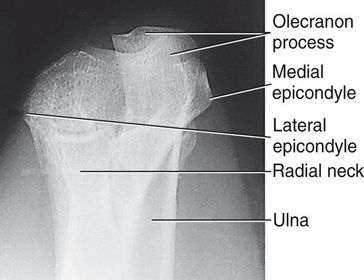

A. medial epicondyle B. trochlea C. coronoid tubercle D. radial head E. capitulum F. lateral epicondyle H. olecranon process